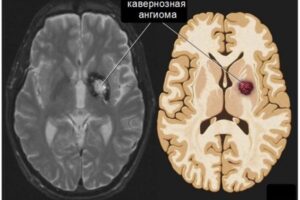

Лечение и диагностика ангиом головного мозга (кавернозная, венозная)

Заболеваемость опухолями головного мозга увеличивается с каждым годом, и этот факт настораживает врачей во многих странах. Доброкачественная опухоль, представляющая собой «клубок кровеносных сосудов», представляет собой церебральную гемангиому. Внешне данная патология напоминает бордовую или красную родинку. Образование наблюдается на слизистых оболочках и коже, при этом новорожденные составляют основную группу риска. Большинство гемангиом исчезают к десяти годам, …